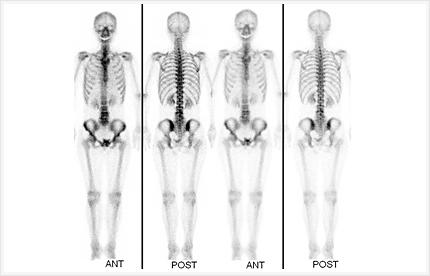

核医学検査(RI)

核医学検査とは?

ガンマ線という放射線を放出する放射性同位元素(ラジオアイソトープ)をごく微量含んでいる検査薬を注射などによってからだの中に入れ、目的の臓器や病変部に取り込まれた薬から放出される微量のガンマ線の分布を体外からガンマカメラで撮影し、肉眼では見えないからだの内部を画像化して調べる検査です。

核医学検査に使うラジオアイソトープの量は、胸部エックス線撮影と同じ程度かそれ以下と微量の放射線量で、短時間で体外に排泄されてしまうので心配はありません。また、投与量が少ないため、副作用が極めて少なく、多くの病気の診断に利用されているのが特徴です。

画像紹介

骨シンチグラフィ

当院で最も検査件数の多い検査です。骨転移の有無を比較的早期に全身検索できることから、転移性骨疾患の検査、原発性骨腫瘍の診断などの目的で行われる検査です。

1.前準備として食事・水分の制限は特に必要ありません。

2.骨シンチグラフィ用の検査薬を静脈注射します。

3.検査薬が骨に集まるのに時間がかかるため、注射後2~3時間経てから撮影を開始します。

4.検査開始直前に必ず排尿していただきます。

5.撮影時間は約30分かかります。必要に応じて部分的な撮像を行います。